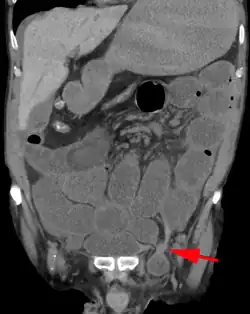

Medical imaging

A physician may diagnose an inguinal hernia, as well as the type, from medical history and physical examination.[20] For confirmation or in uncertain cases, medical ultrasonography is the first choice of imaging, because it can both detect the hernia and evaluate its changes with for example pressure, standing and Valsalva maneuver.[21]

When assessed by ultrasound or cross sectional imaging with CT or MRI, the major differential in diagnosing indirect inguinal hernias is differentiation from spermatic cord lipomas, as both can contain only fat and extend along the inguinal canal into the scrotum.[22]

On axial CT, lipomas originate inferior or lateral to the cord, and are located inside the cremaster muscle, while inguinal hernias lie anteromedial to the cord and are not intramuscular. Large lipomas may appear nearly indistinguishable as the fat engulfs anatomic boundaries, but they do not change position with coughing or straining.[22]